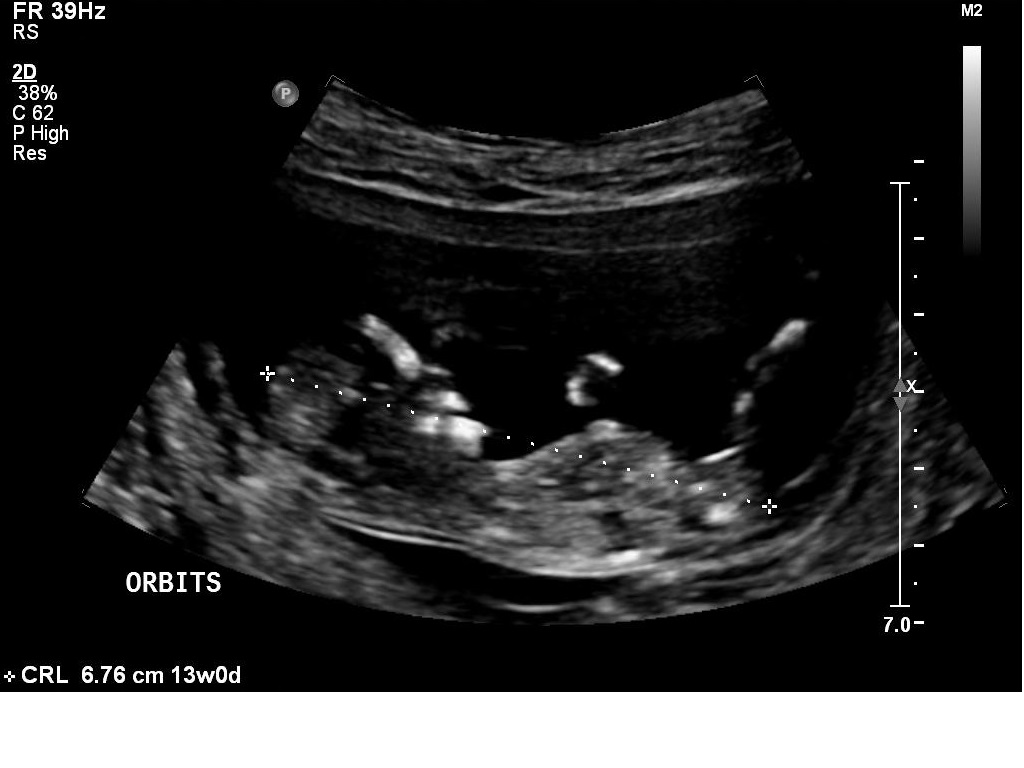

I had my 12w1d ultrasound today, but baby measured ahead at 13 weeks. Bub was very uncooperative and made it hard for the technician to get the NT measurements, which was good in a way because I got to see lots of bub! We got heaps of pictures and I will upload a few here.

I *think* I can tell the gender by the nub pictures but I'd love lots of guesses!!

What do you all think?